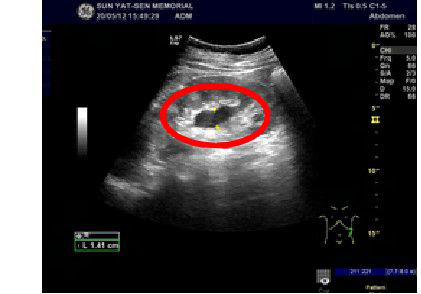

患者泌尿系彩超结果显示肾积水

在与张丽沟通后,黄海教授及其团队为她安排了第一期骶神经刺激器置入术,术后张丽的大便失禁症状立即消失。排尿困难症状有所改善。彩超复查显示,张丽双肾的积水消失,残余尿消失,尿急时无漏尿情况出现。经过观察和恢复后,张丽顺利出院。